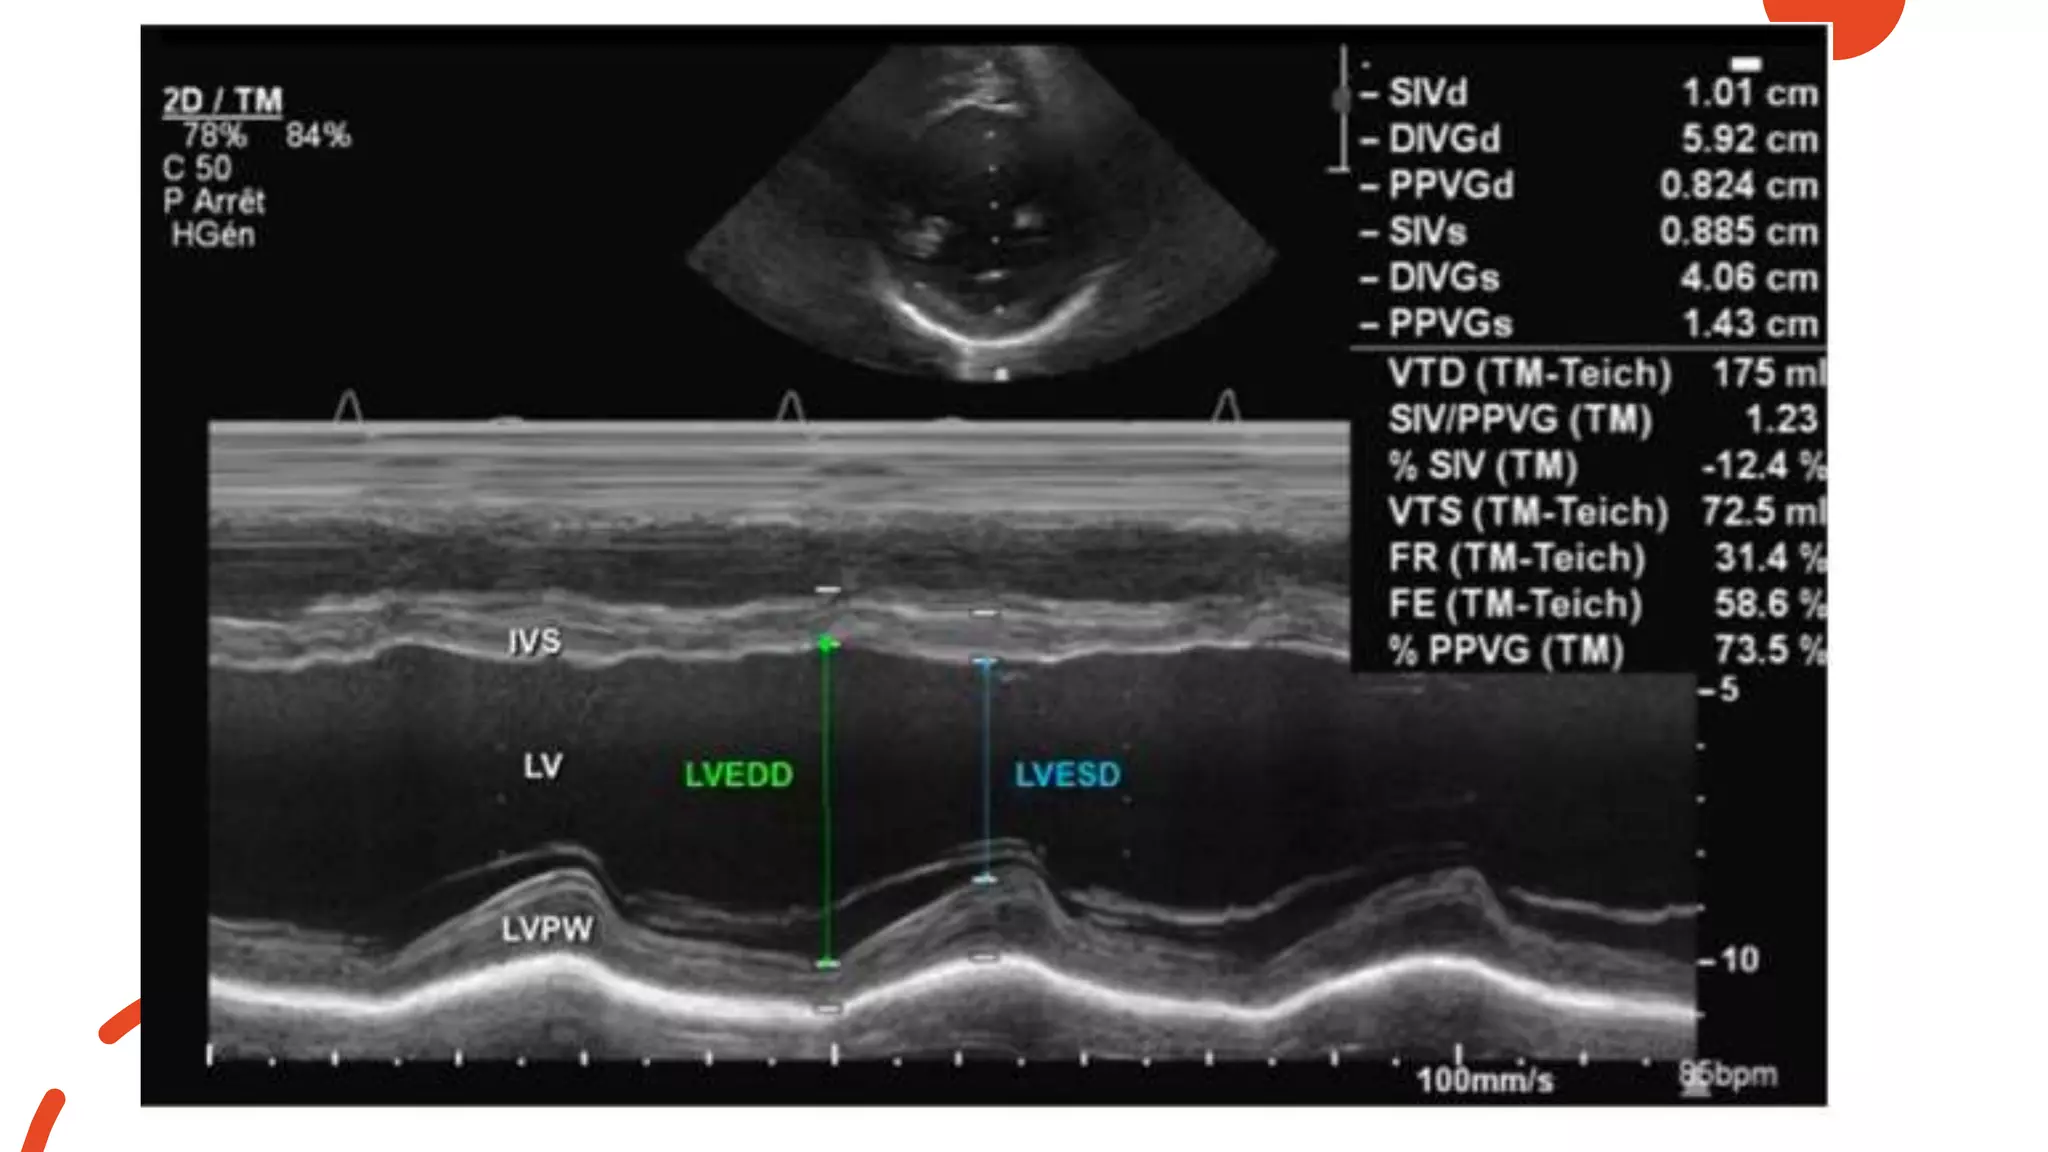

Normal M-Mode Examination of the Left

Ventricle

• left ventricular dimensions:

measured at end-diastole and

end-systole

• left ventricular wall thicknesses

(IVS and PW) : measured at end

diastole

• end-diastole: defined as the

frame at which the MV closes

• end-systole: the frame preceding

MV opening

• #34 M-mode echocardiography from a parasternal short-axis view showing the left ventricular cavity over the cardiac cycle (see ECG tracing) during systole and diastole. Abbreviations: IVS, interventricular septum; LV, left ventricle; LVEDD, left ventricle end-diastolic dimension; LVESD, left ventricle end-systolic dimension; LVPW, left ventricle posterior wall.